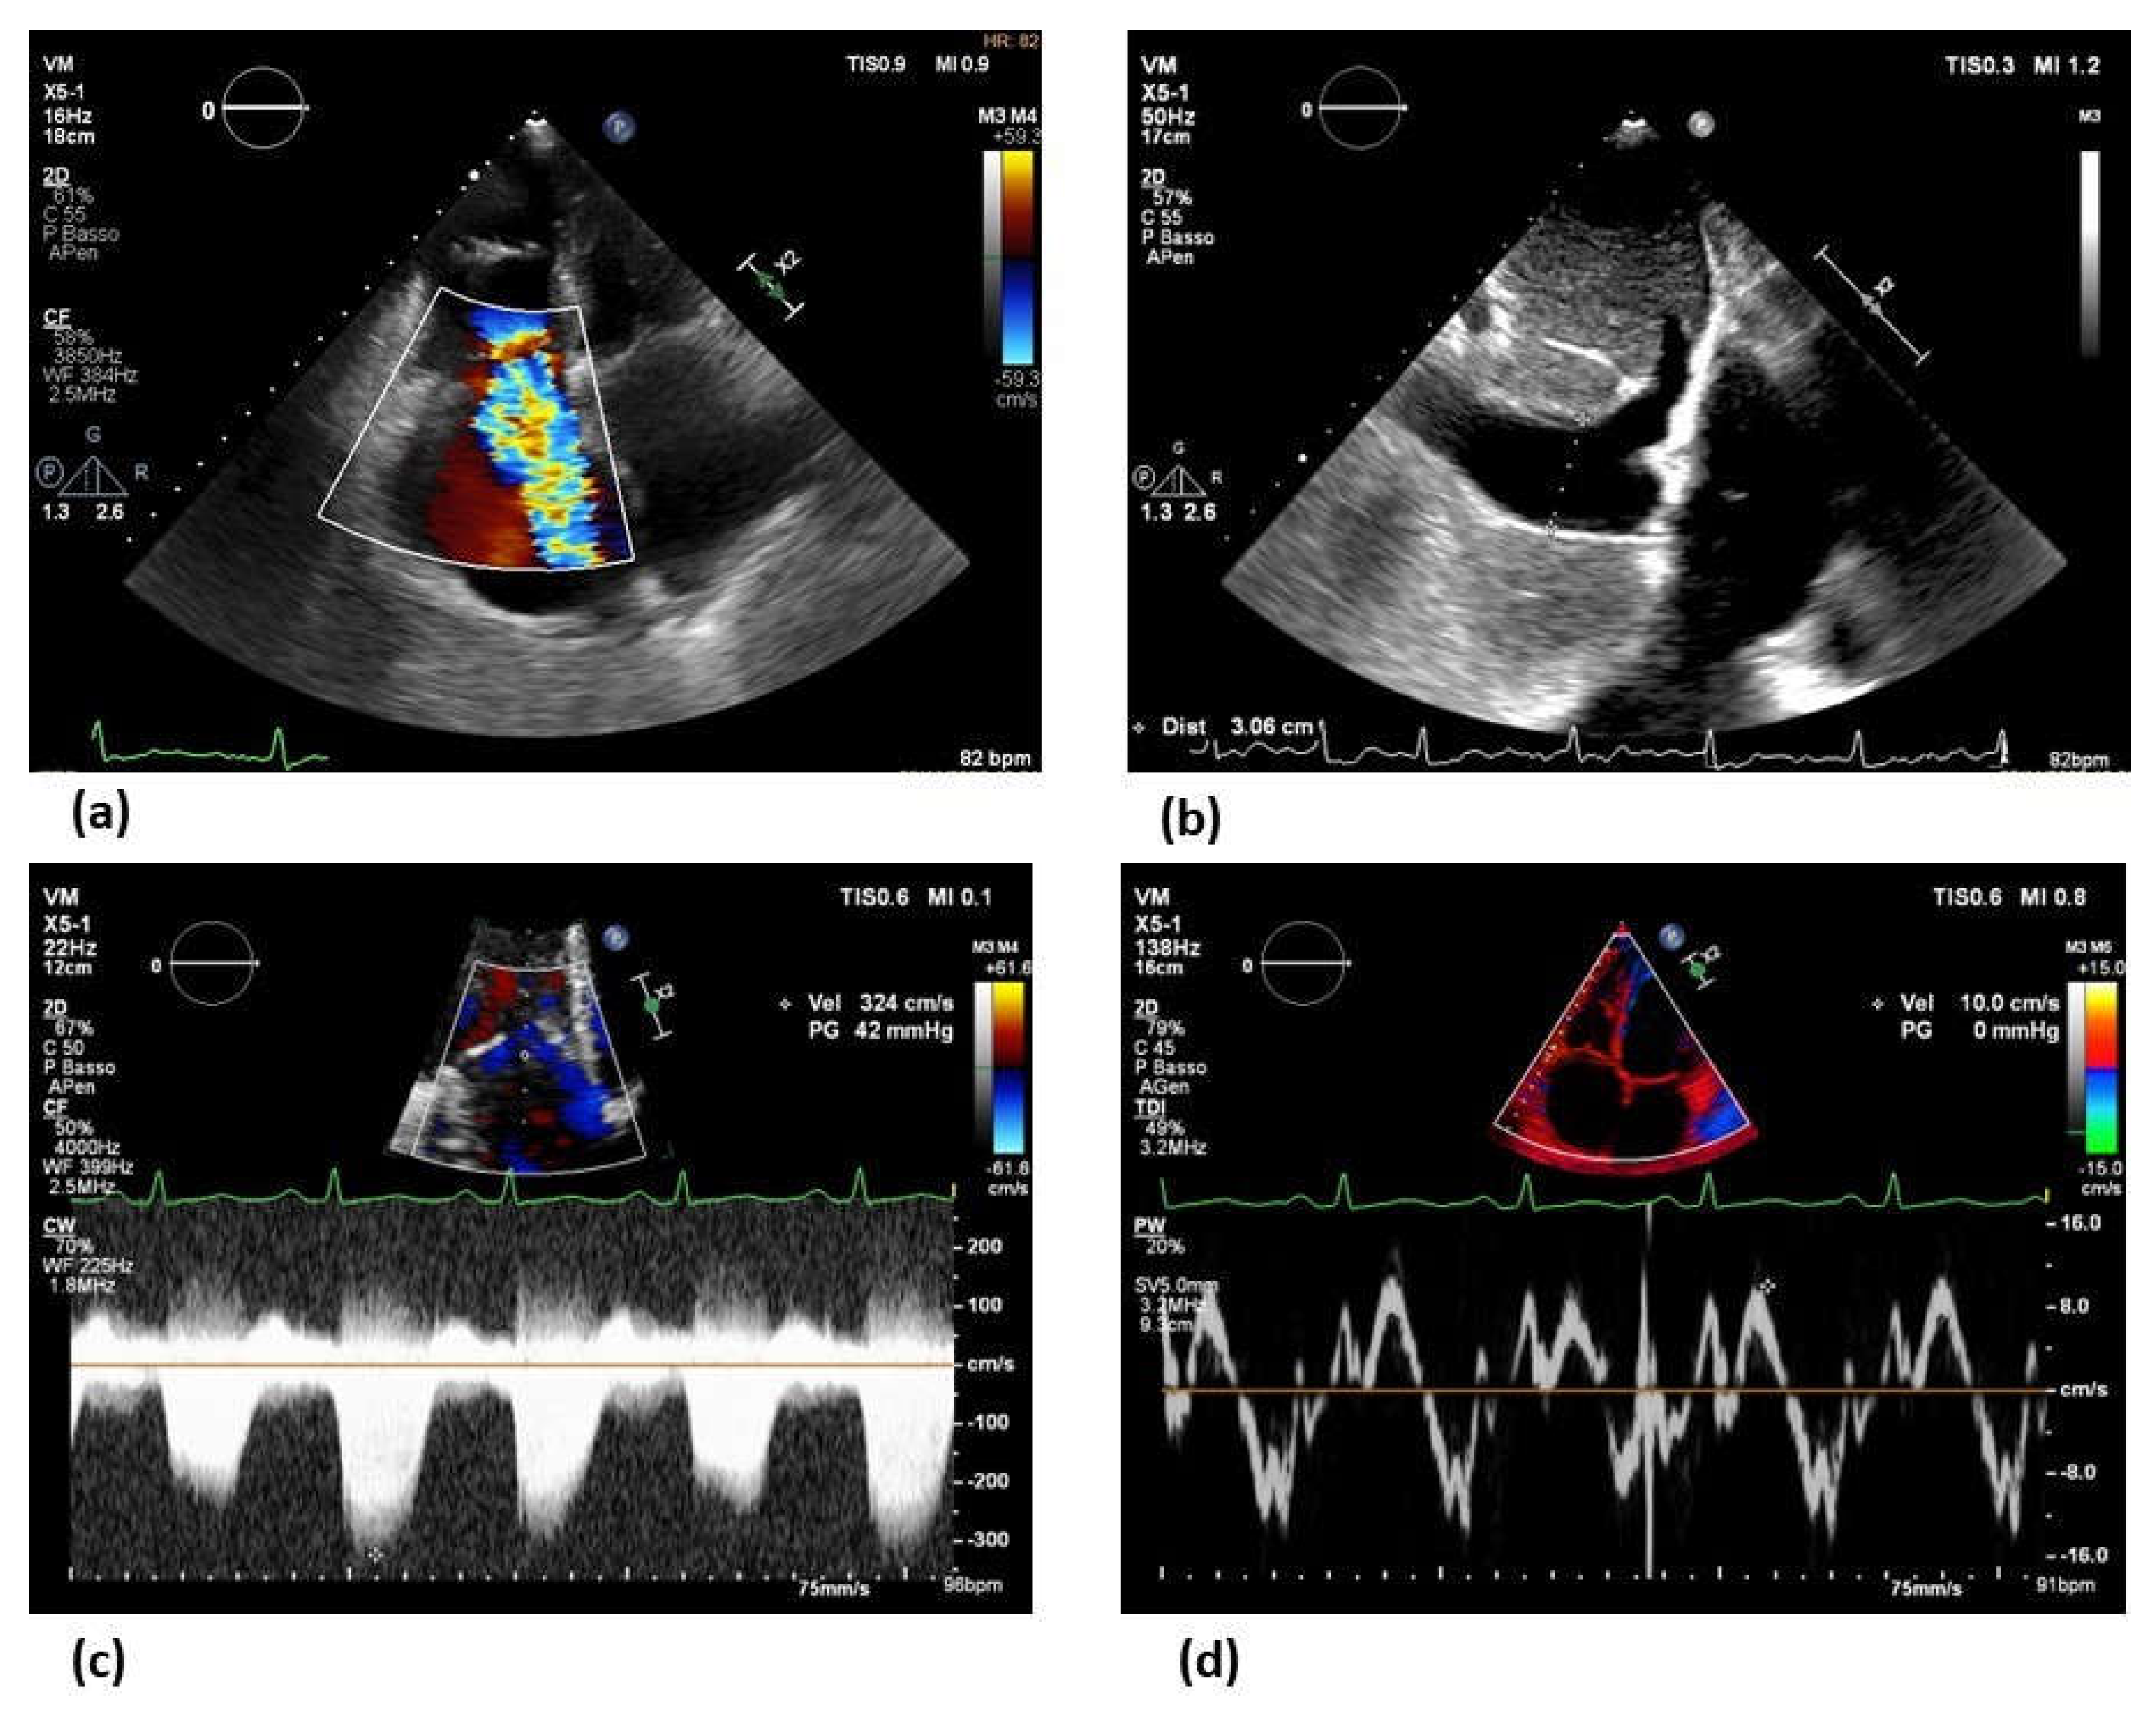

- Frea, S.; Pidello, S.; Bovolo, V.; Iacovino, C.; Franco, E.; Pinneri, F.; Galluzzo, A.; Volpe, A.; Visconti, M.; Peirone, A.; et al. Prognostic incremental role of right ventricular function in acute decompensation of advanced chronic heart failure. Eur J Heart Fail 2016, 18, 564–572. [Google Scholar] [CrossRef]

- Maeder, M.T.; Holst, D.P.; Kaye, D.M. Tricuspid regurgitation contributes to renal dysfunction in patients with heart failure. J Card Fail 2008, 14, 824–830. [Google Scholar] [CrossRef]

- Pellicori, P.; Carubelli, V.; Zhang, J.; Castiello, T.; Sherwi, N.; Clark, A.L.; Cleland, J.G. IVC diameter in patients with chronic heart failure: relationships and prognostic significance. JACC Cardiovasc Imaging 2013, 6, 16–28. [Google Scholar] [CrossRef]

- Cowie, B.; Kluger, R.; Rex, S.; Missant, C. Noninvasive estimation of left atrial pressure with transesophageal echocardiography. Ann Card Anaesth 2015, 18, 312–316. [Google Scholar] [CrossRef]

- Park, J.H.; Marwick, T.H. Use and Limitations of E/e' to Assess Left Ventricular Filling Pressure by Echocardiography. J Cardiovasc Ultrasound 2011, 19, 169–173. [Google Scholar] [CrossRef]